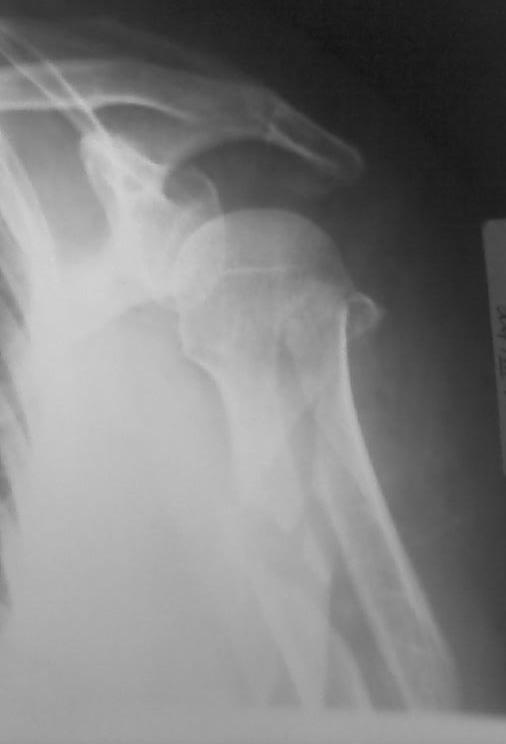

Здравствуйте уважаемые коллеги!!! Недавно стали применять в своей работе малоинвазивные методы лечения. На прошлой неделе прооперировали пожилую женщину с сопутствующим сахарным диабетом по поводу оскольчатого перелома в/3 плечевой кости штифтом PHN фирмы "Mathys". Имеется вот такое стояние костных отломков (см. рентгенограммы). Мнения коллег в отделении разделились: одни считают, что стояние отломков крайне неудовлетворительное и сращение кости при таком стоянии вряд ли возможно, другие считают, что при закрытом методе остеосинтеза и стабильной фиксации отломков результат будет благоприятный и сращение кости, даже при таком стоянии костных отломков, будет обязательно. Я придерживаюсь последнего мнения. Коллеги, каково ваше мнение? У нас это первые больные после подобных операций, поэтому большого опыта не имеем. Поделитесь своим опытом! И если это возможно, то для убедительности выложите рентгенограммы после операции и после сращения переломов с подобным стоянием отломков. Заранее СПАСИБО!!!

Положение отломков диафиза приемлемое.

Похоже, немножко выстоит стержень проксимально - возможен импинджмент, для уточнения можно сделать еще фас с максимальным отведением.

Беспокоит выбранная слишком латеральная для этого штифта точка введения, и выстояние кончика штифта... А клинок заблокировали концевым колпачком?

Уважаемый коллега! для закртытого БИОС данное стояние отломков вполне приемлемое, но импиджмент неизбежен. С уважением Ерсин Жунусов.

Уважаемый Евгений! Положение отломков благоприятно для сращения. Варусное смещение отломков можно было бы уменьшить изначально использовав более медиальную точку введения стержня. Импиджмент, скорее всего, будет, удаляйте стержень по-возможности раньше. Для лечения данного перелома можно было бы обратить внимание на ретроградный способ введения стержня, но к данной методике нужно подходить с осторожностью, необходим опыт БИОС.